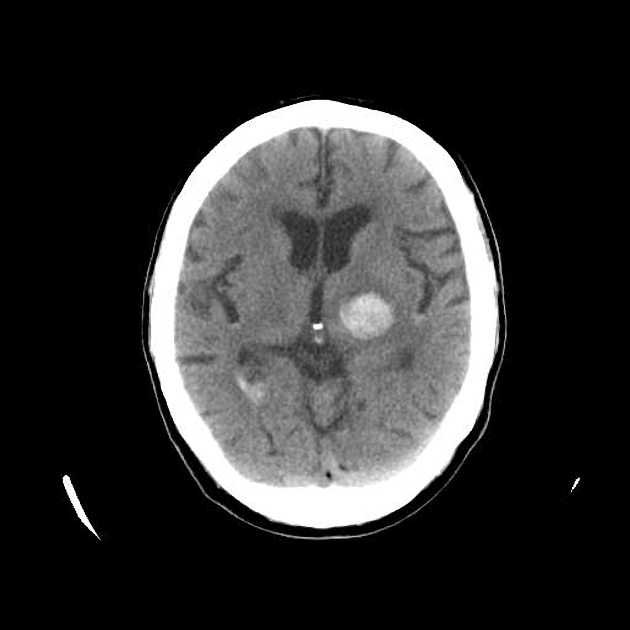

Прозрачная перегородка кт

Прозрачная перегородка кт 115 фотографий